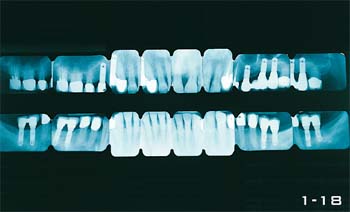

Nun liegen wichtige klinische Befunde vor: Röntgenstatus (mindestens 16 Bilder) (Abb. 1-10 bis 1-14 und 1-18), Panoramaaufnahmen (Abb. 1-15 bis 1-17), Parodontalstatus (Abb. 1-9) und vor allem Information über die Fähigkeiten und den Willen des Patienten zu einer effektiven Plaquekontrolle (Abb. 1-19 bis 1-24).

Abb. 1-18 Röntgenstatus nach Abschluss der Behandlung mit einem zufrieden stellenden Ergebnis.